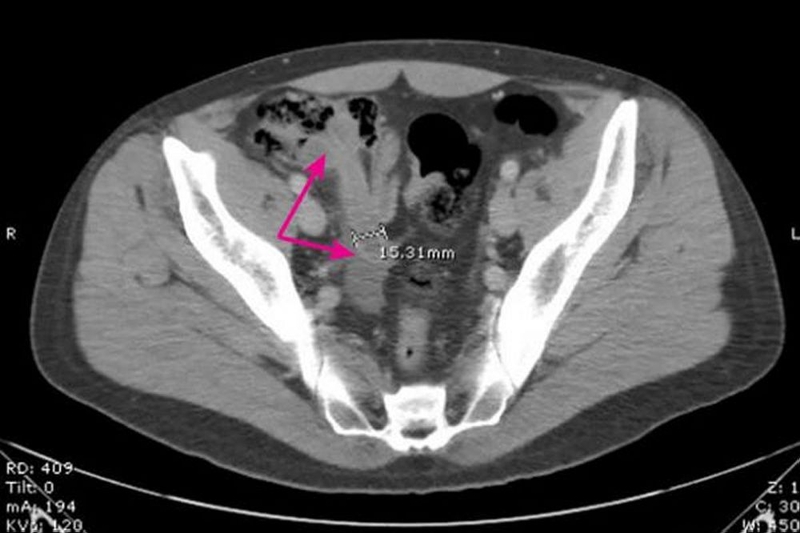

Viêm ruột thừa được coi là một trong những bệnh lý cần cấp cứu ngoại khoa thường gặp nhất. Chẩn đoán viêm ruột thừa hiện nay chủ yếu dựa trên các dấu hiệu lâm sàng, mặc dù những tiến bộ vượt bậc trong chẩn đoán hình ảnh đã hỗ trợ rất nhiều trong việc xác định bệnh một cách chính xác và nhanh chóng.

Một số xét nghiệm để tăng mức độ khẳng định cho trường hợp viêm ruột thừa bao gồm:

Như vậy chẩn đoán viêm ruột thừa đòi hỏi sự kết hợp giữa triệu chứng lâm sàng, cận lâm sàng và các phương pháp hình ảnh để xác định chính xác và kịp thời, đặc biệt trong các trường hợp phức tạp.